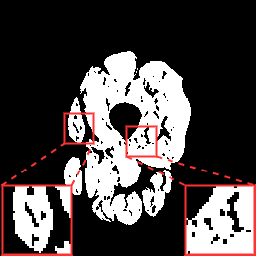

(a) Image

(b) GT

(c) Without

(d) With

To verify the effectiveness of each component in our proposed framework, we conducted a set of ablation studies. Table 1 summarizes the results regarding the data augmentation strategies. Adjusting the contrast of input images reduces the effect from intensity inhomogeneity as evidenced by the improvement on the Dice metrics. Further ablation studies were conducted regarding the PLD stage. When training the model without confidence evaluation (CE), the performance decreases considerably as is supervised by masks that contain potentially incomplete structures. By constraining the supervision signal with CE and (visual examples in Fig. 4), the model is capable of better exploiting the masks.